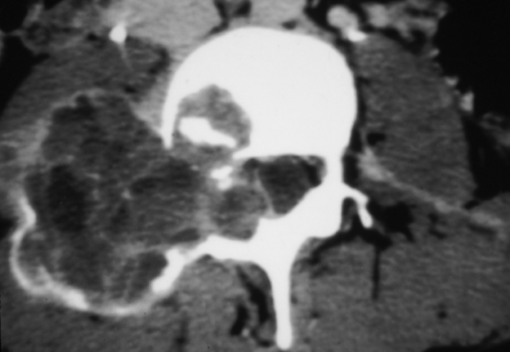

Synovial Cyst

Synovial Cyst Posteriorly Projecting